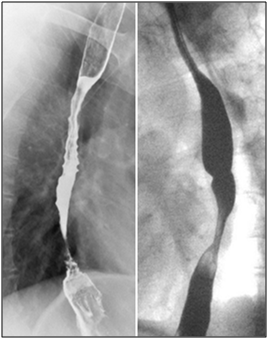

A 46 year-old male with end stage renal disease underwent deceased donor kidney transplant followed by immunosuppression with MMF, tacrolimus, and prednisone. Shortly after transplantation, he noted new solid food intermittent dysphagia with slow progression over 6 months. He was later hospitalized with progressive worsening of nausea, vomiting and dysphagia. Esophagogastroduodenoscopy (EGD) showed LA Class D esophagitis about 10 cm above the gastro-esophageal junction with a stenosisat 30cm from the incisors. Biopsies showed acute and chronic inflammation without increased eosinophils or evidence of Barrett’s mucosa. Stains for fungi, cytomegalovirus (CMV) and herpesvirus (HSV) were negative. He was treated with esomeprazole 40mg twice a day but was re-hospitalized one month later with persistent symptoms. A repeat EGD demonstrated once again LA Class D esophagitis with worsening stricture in the proximal part of the lower third of the esophagus along with candida plaques. Biopsies revealed severe esophagitis without CMV/HSV (Figure 1). The stricture was dilated up to 44 Fusing Maloney dilators and fluconazole and nystatin were added to his proton pump inhibitor (PPI).

Figure 1 20x (left) and 40x (right) views of desquamated squamous epithelium with associated acute fibrino-inflammatory infiltrates consisting predominantly of neutrophils with background reactive cytologic changes.